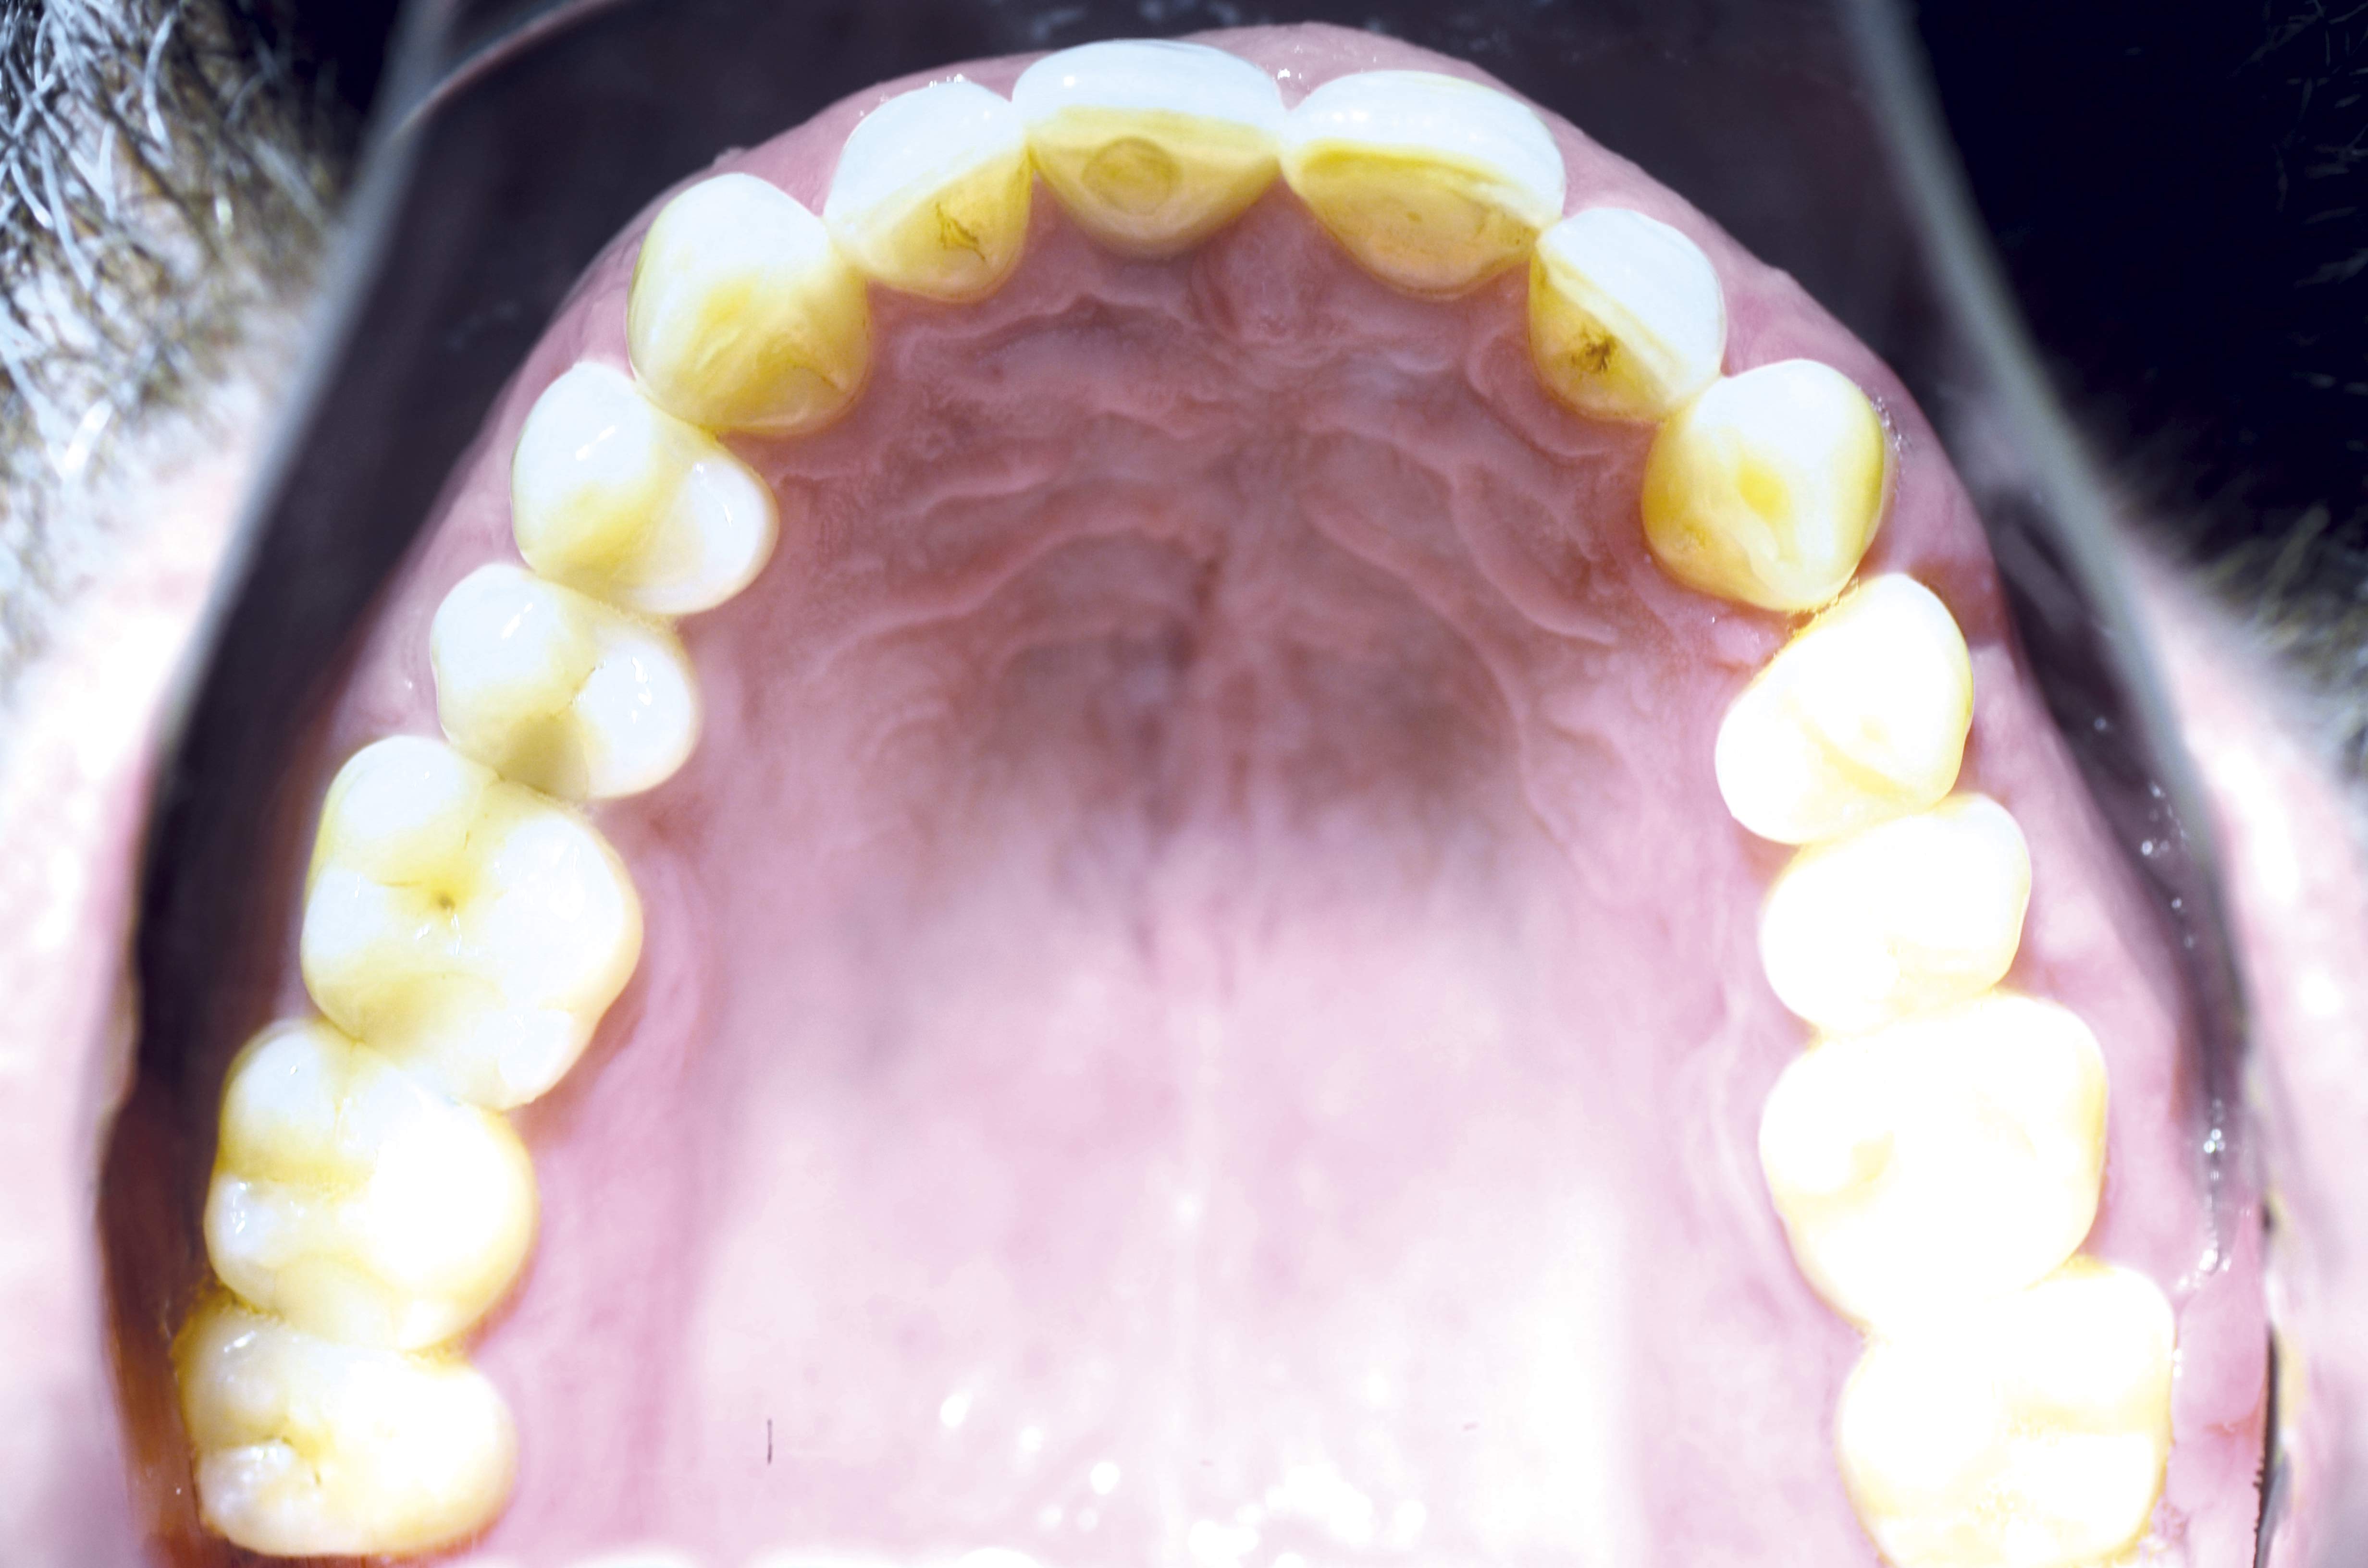

17/18 - Prosthetics 1 year after uncovering the implant – occlusal view

Block augmentation with maxgraft® and cerabone® – PD Dr. Dr. F. Kloss